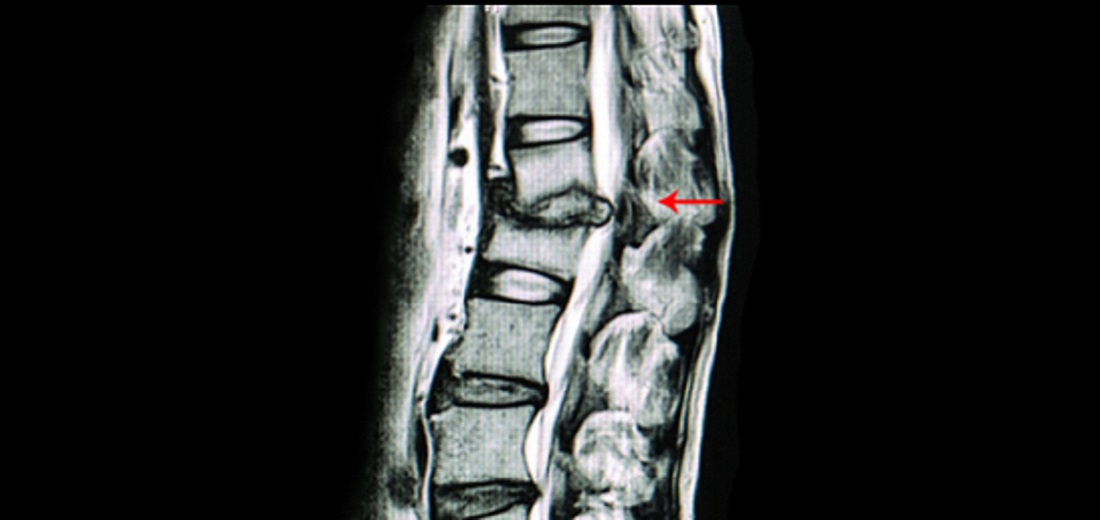

Vetebra Body Stenting

Aster CMI Hospital Conducts South India’s Fir...

Keeping up with its commitment to providing world-class clinical medical service...